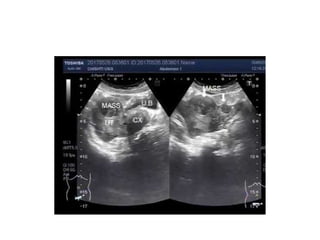

Leiomyoma (Fibroids)

●Benign tumors of the uterine myometrium

●Estrogen dependent

●Common in child bearing age, black, and

nulliparous

●Classified according to site : submucous,

intramural and subserous fibroids

●Can cause bleeding by increased vascularity of

uterus(red degeneration in pregnancy),

endometrial hyperplasia, ovarian congestion or

malignant changes

●Most of fibroids are asymptomatic that need no

intervention

●Intervention needed if give rise to symptoms

like bleeding, pain, infertility, and huge size that

lead to compressive symptoms

●Investigation by ultrasonography, HSG,

hysteroscopy and CT/MRI

●Definitine treatment are surgical intervention

●Myomectomy -want to keep uterus

●Hysterectomy -when myomectomy

contraindicated

Leiomyoma (Fibroids) ●Benign tumorsof the uterine myometrium ●Estrogen dependent ●Common in child bearing age, black, and nulliparous ●Classified according to site : submucous, intramural and subserous fibroids ●Can cause bleeding by increased vascularity of uterus(red degeneration in pregnancy), endometrial hyperplasia, ovarian congestion or malignant changes

• 20.

●Most of fibroidsare asymptomatic that need no intervention ●Intervention needed if give rise to symptoms like bleeding, pain, infertility, and huge size that lead to compressive symptoms ●Investigation by ultrasonography, HSG, hysteroscopy and CT/MRI ●Definitine treatment are surgical intervention ●Myomectomy -want to keep uterus ●Hysterectomy -when myomectomy contraindicated